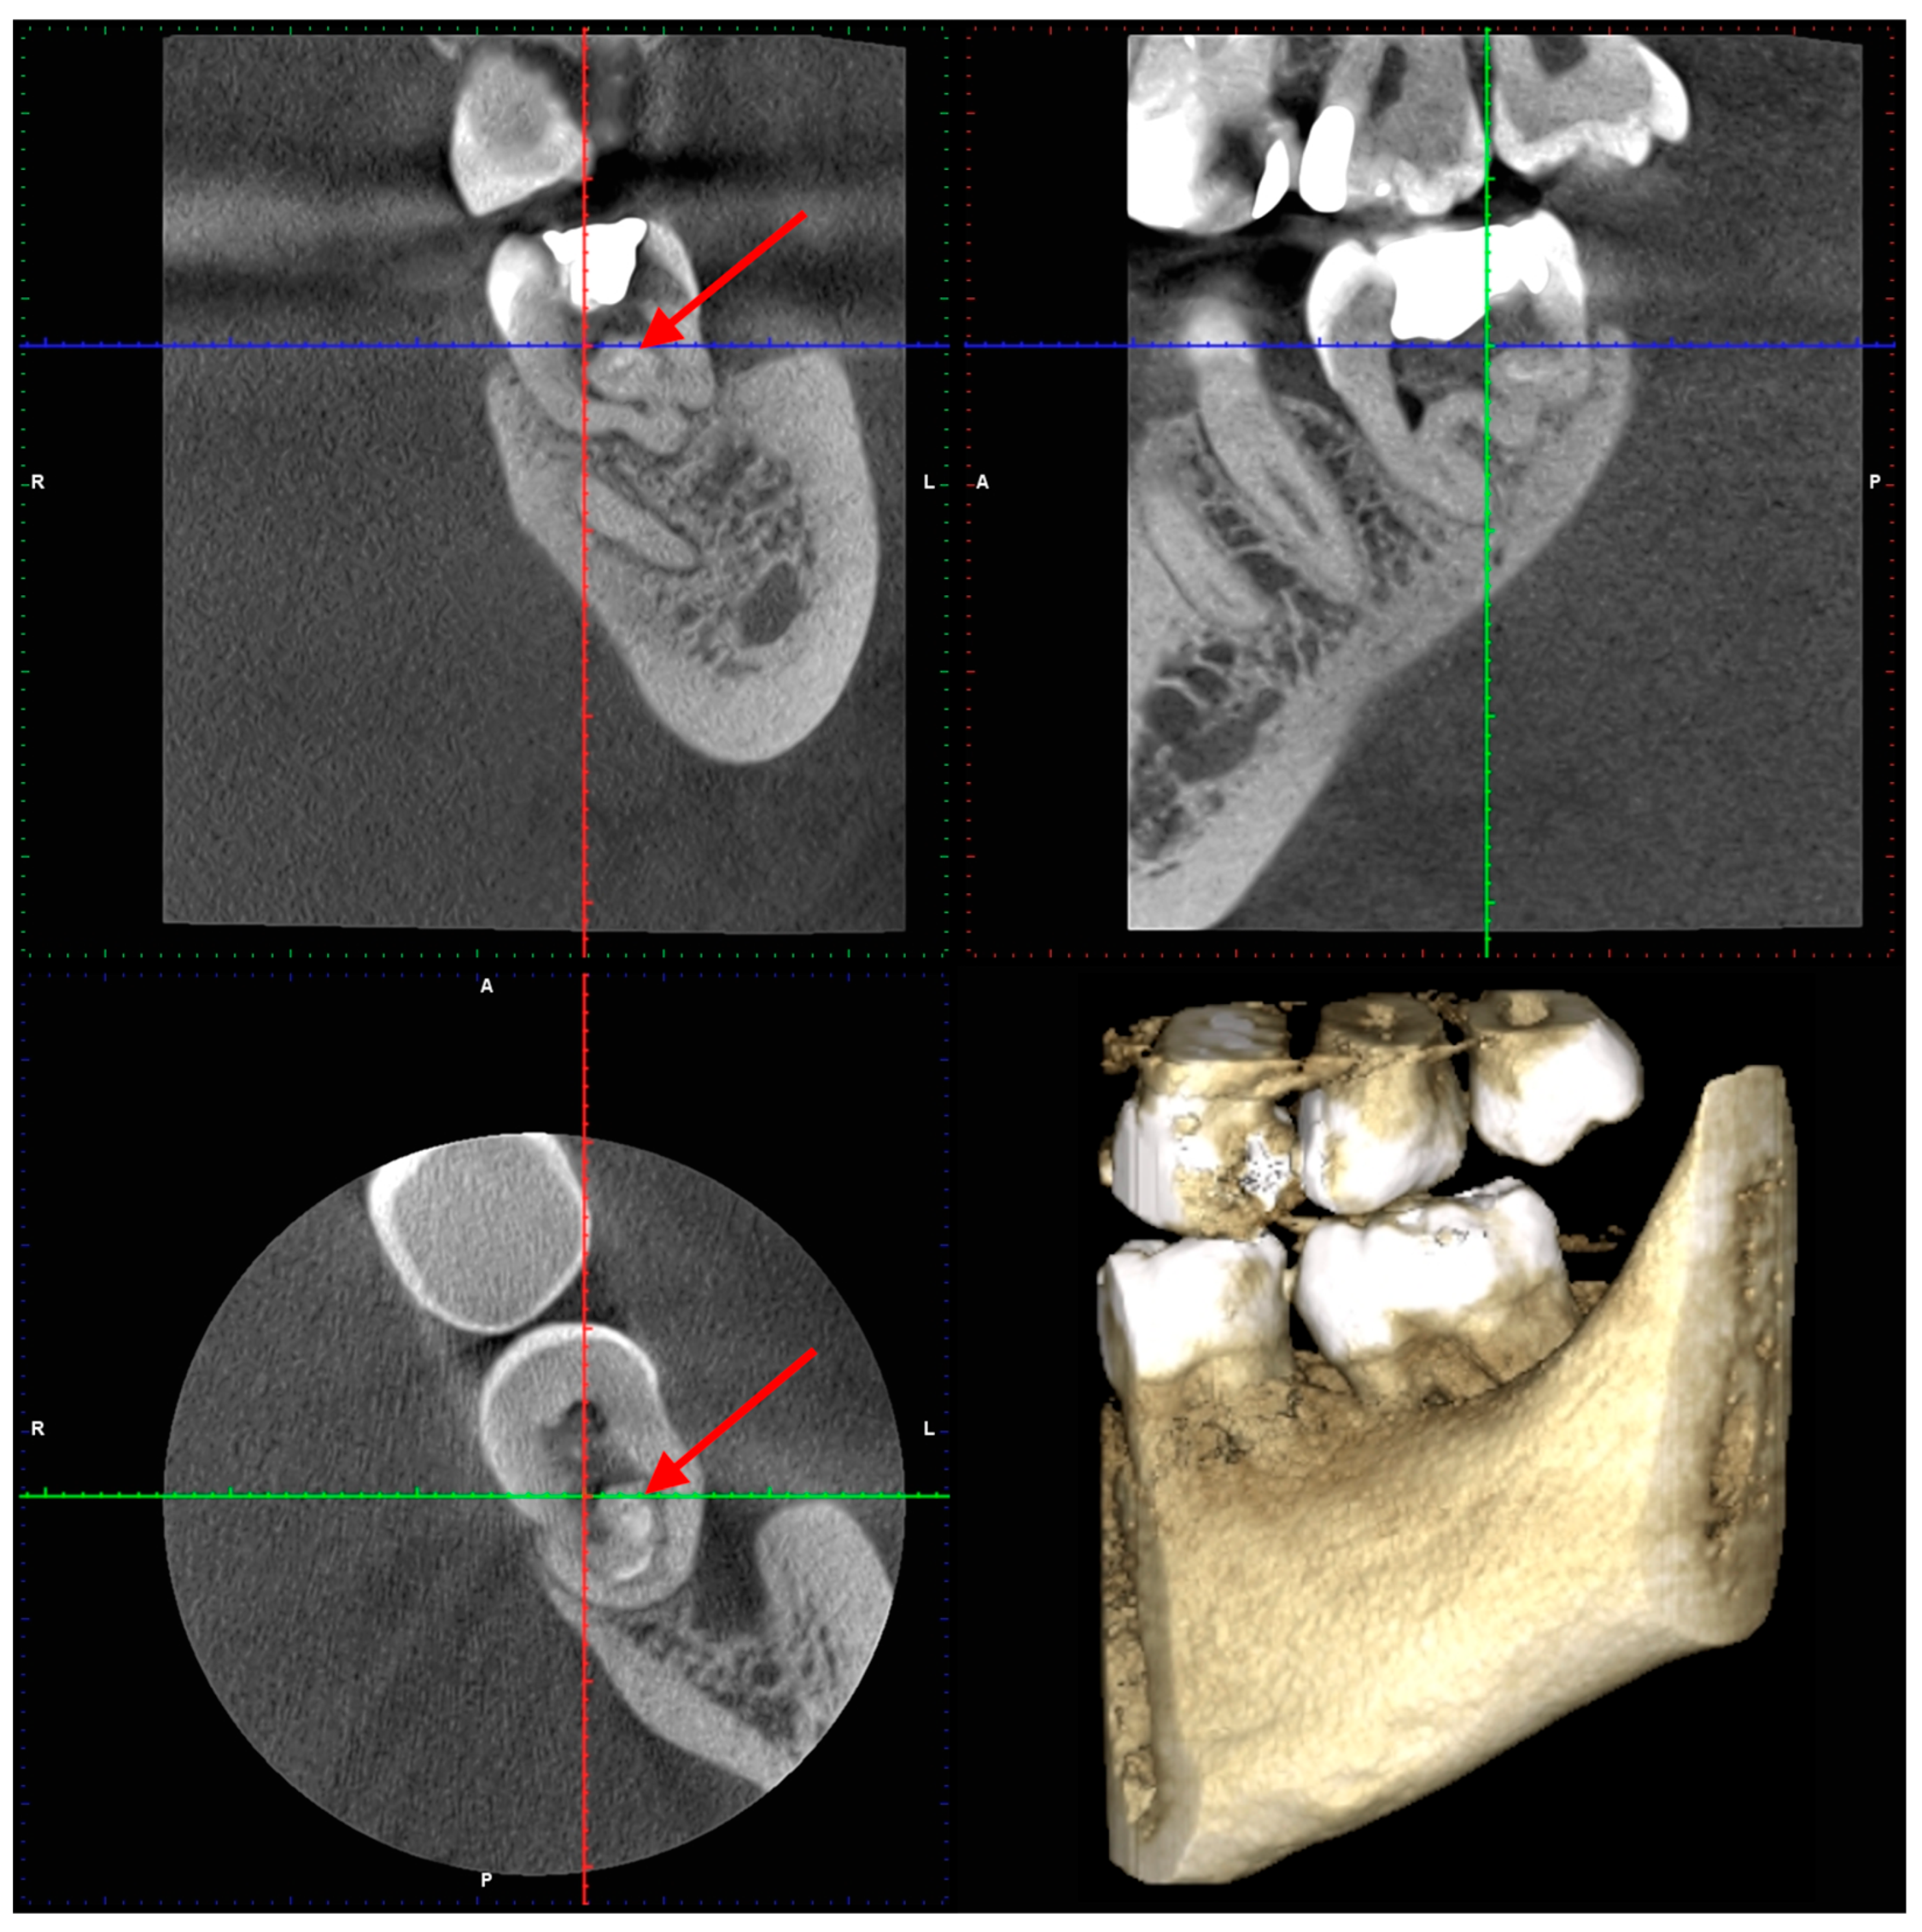

2. Case Presentation

2.1. The First Visit